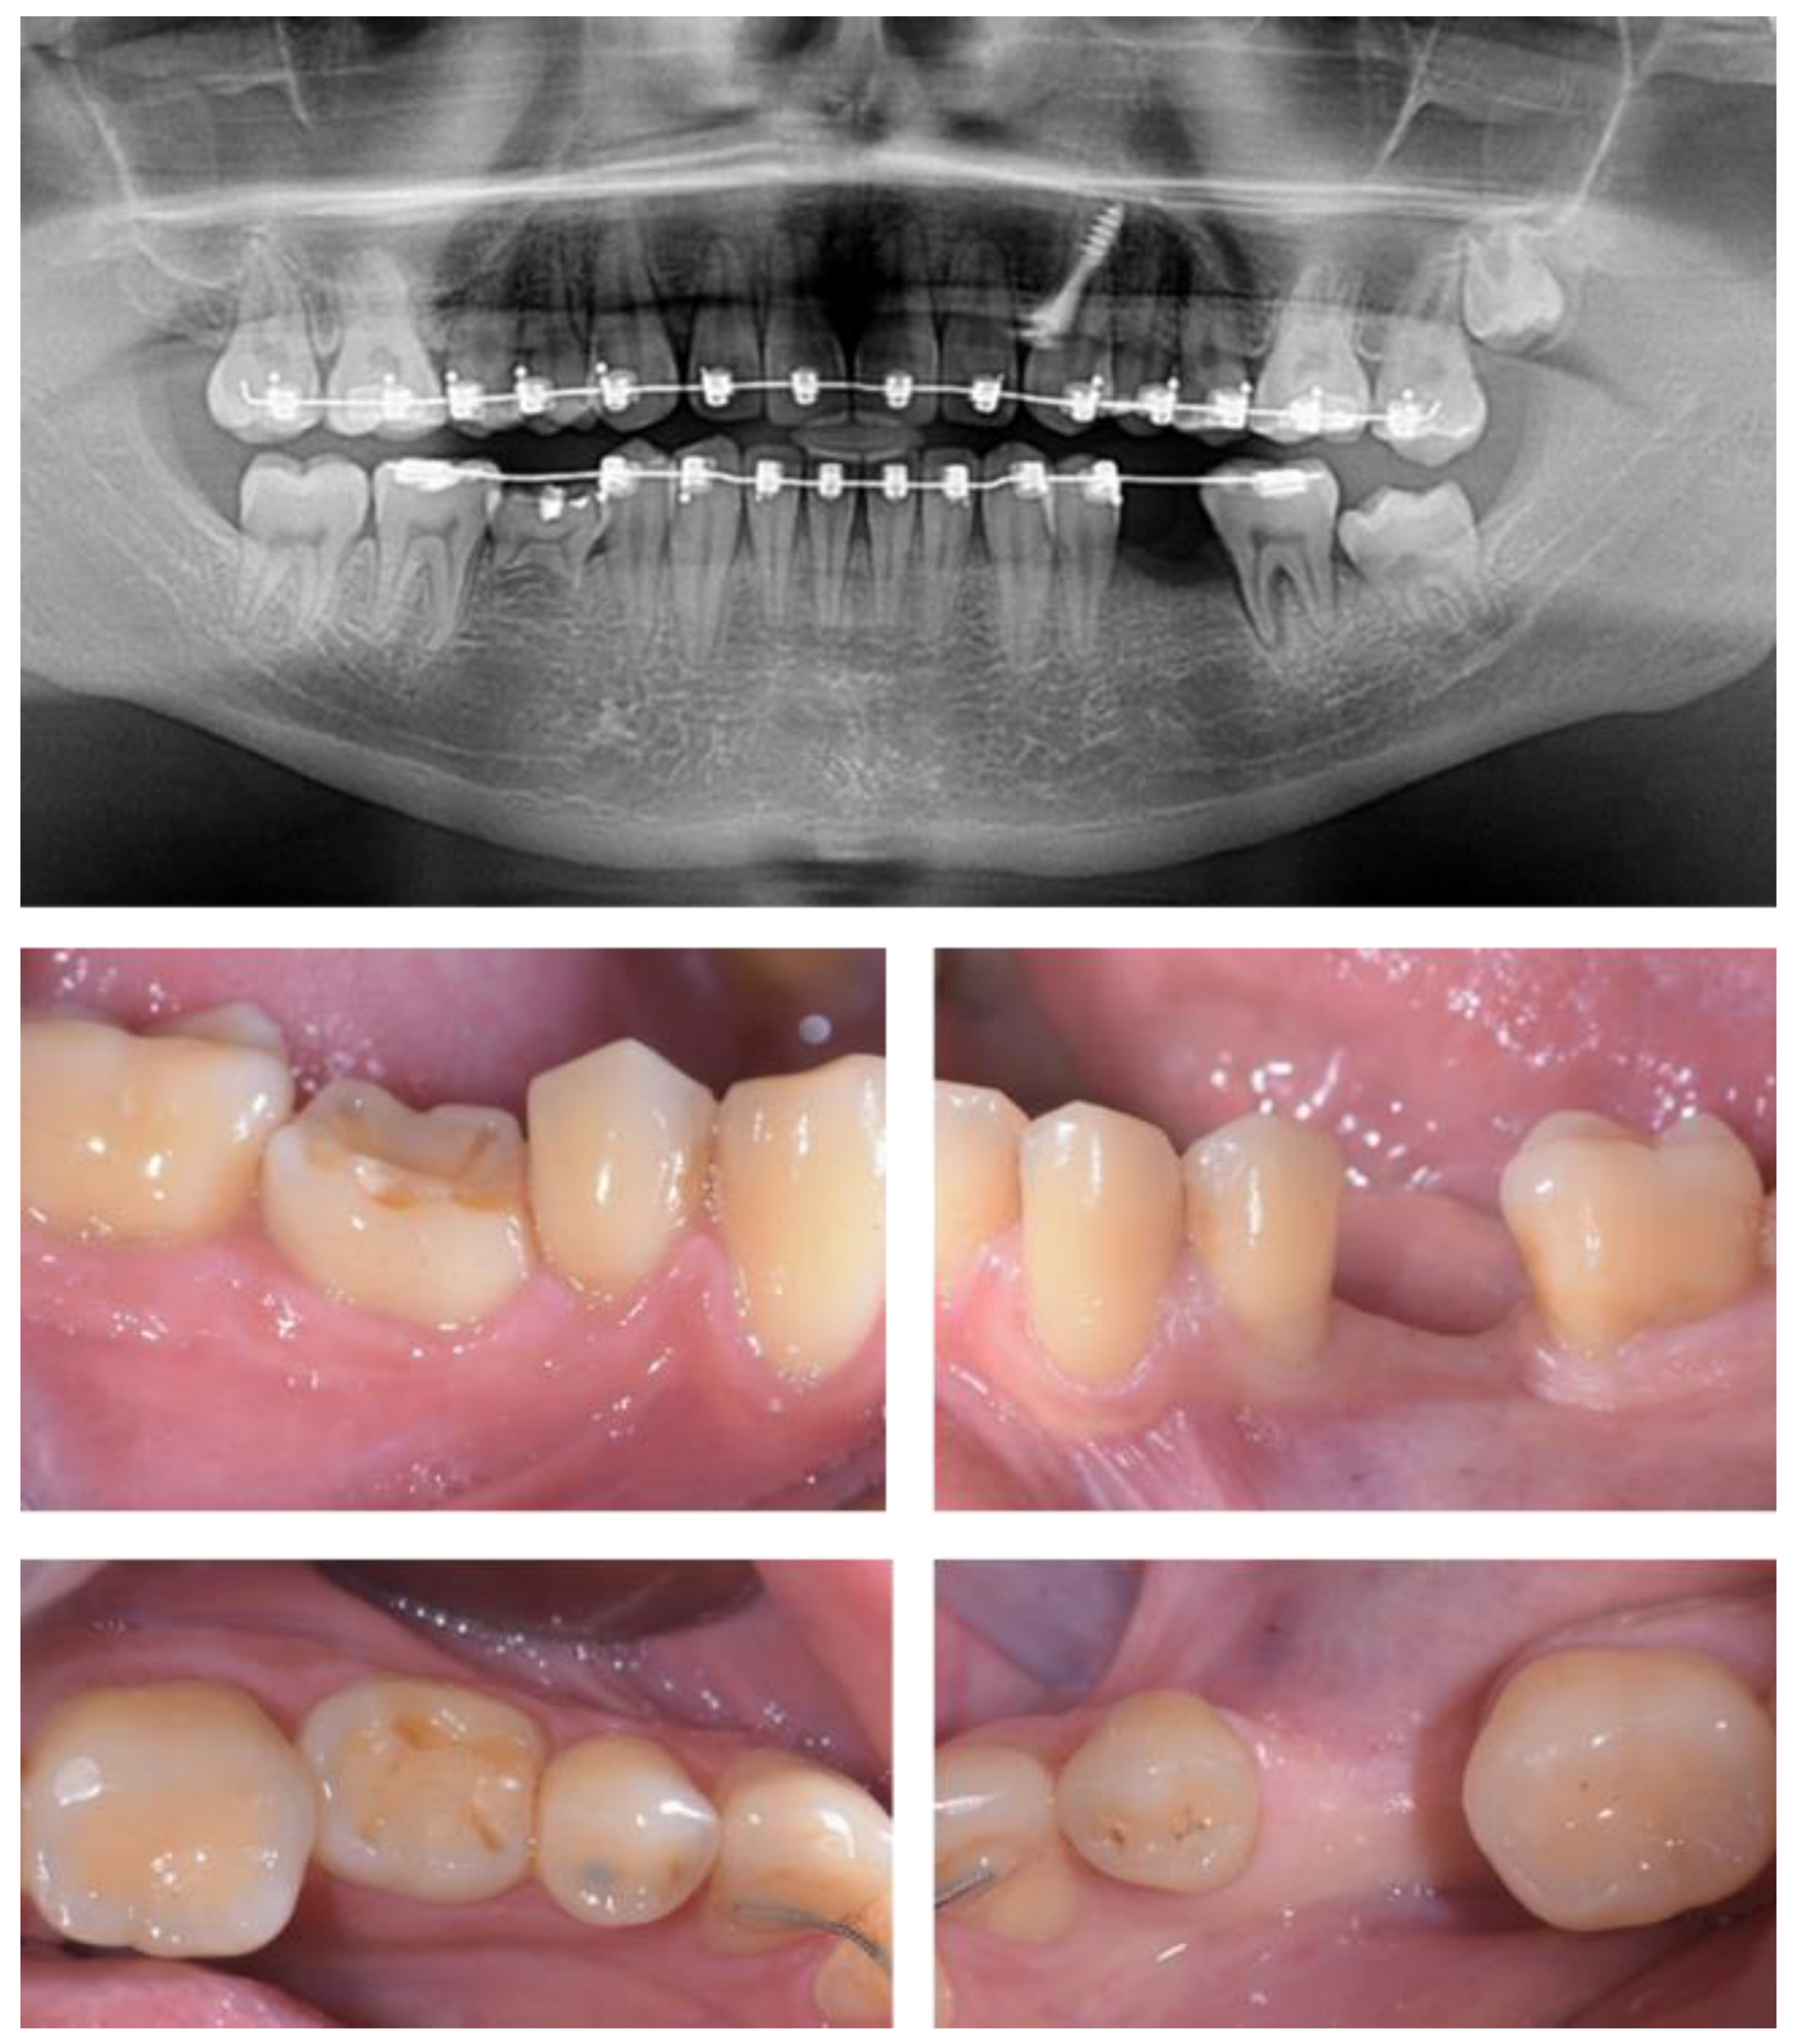

2.5. Individual Cases Description

- Case 1:

- Case 2:

- Case 3:

- Case 4:

- Case 5: